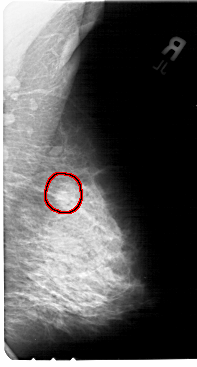

A_1397_1.RIGHT_MLO

RIGHT_MLO LINES 5491 PIXELS_PER_LINE 2941 BITS_PER_PIXEL 12 RESOLUTION 43.5 OVERLAY

FILE: A_1397_1.RIGHT_MLO.OVERLAY

TOTAL_ABNORMALITIES 1

ABNORMALITY 1

LESION_TYPE MASS SHAPE LOBULATED MARGINS OBSCURED

ASSESSMENT 4

SUBTLETY 3

PATHOLOGY BENIGN

TOTAL_OUTLINES 1

BOUNDARY